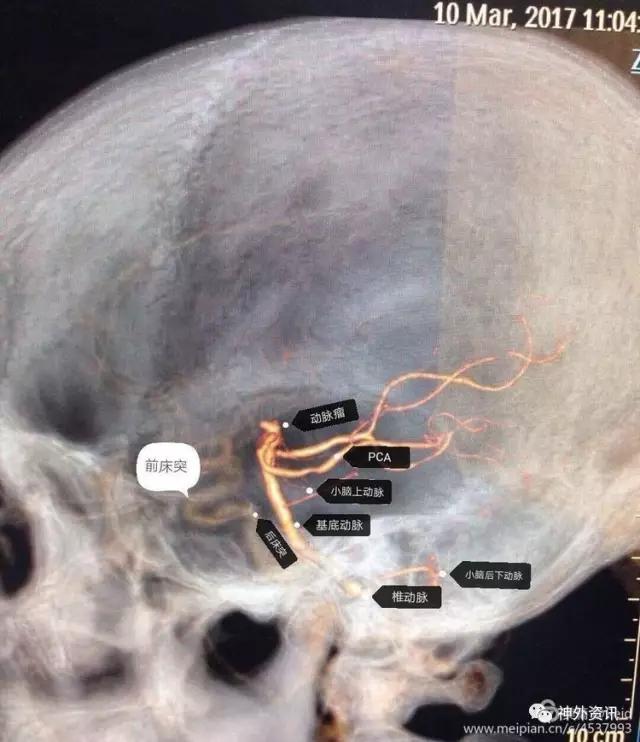

侧位显示基底动脉尖动脉瘤形态,可见动脉瘤窄蒂,瘤顶指向前上方,瘤颈与后床突相距约3.0cm,属于高位基底动脉尖动脉瘤。